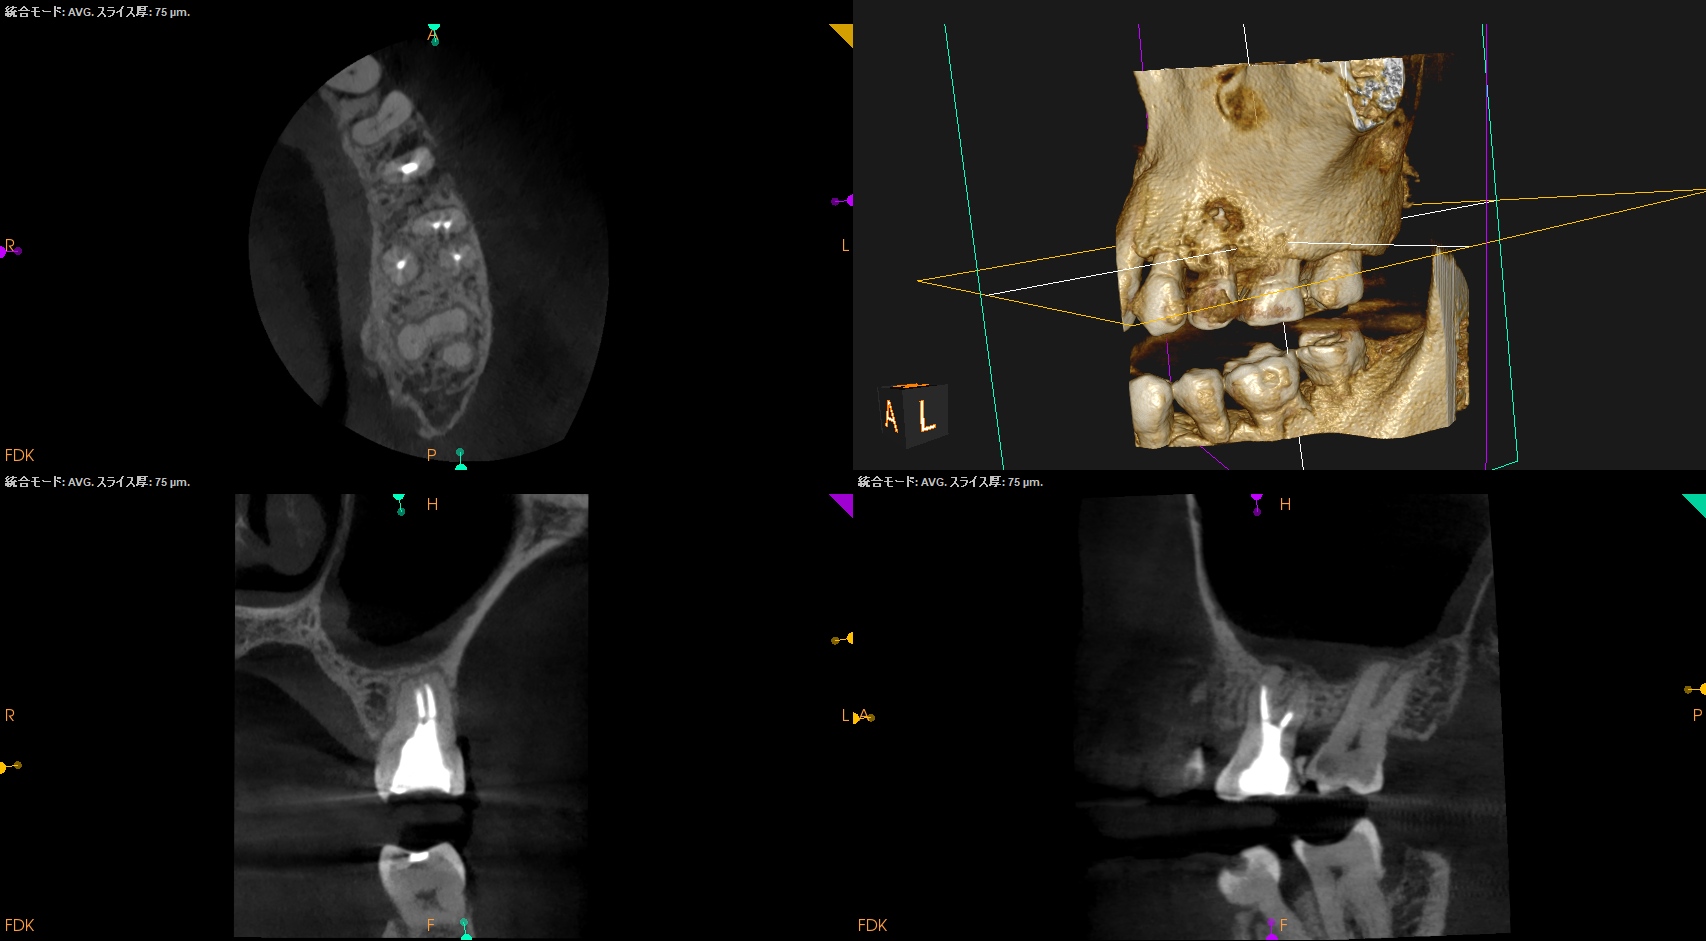

CBCTも撮影した。

これはマストの医療行為である、と私からは告げておこう。

#14

MB

MB2

DB

P

B

ヨシダ社のパノラマと前述のパノラマを比較してほしい。

話にならないくらい、どちらが優れた画質であるか?ということを。

さておき、#13にも病変があるのがわかるので#13も分析した。

#13

#13は#14よりも大きな根尖病変がある。

ここも治療が必要だろう。

Pulp Dx: Previously initiated therapy

Periapical Dx: Symptomatic apical periodontitis

Recomended Tx: Re-RCT

では、再根管治療が必要な治療とわかるのだが、その成功率はどれくらいか?と言えば

穿通できれば86%

穿通できなければ60%

である。

が、いずれにしてもこの治療での最大のポイントになるのはMB2がどこにあるか?である。

MB2の根尖部にはCBCTで根尖病変があるからだ。

さて皆さんは気が付いただろうか?

作業長が術前に予測したCBCTでの作業長に近似していること

を。

これが、

CBCTの威力